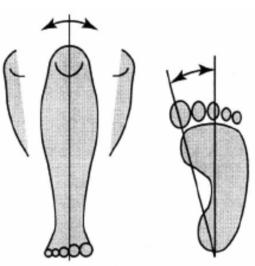

二、跟骨骨密度儀檢測時足和身體的位置

檢測時,足緊貼于產品的最下端(如圖緊貼3個部位)。 骨密度儀的護腿板與足軸和身體的中心軸,需呈一條直線。

跟骨骨密度檢測正確坐姿示意圖

跟骨骨密度檢測不正確坐姿示意圖